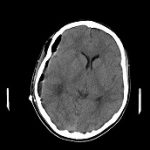

脳血管撮影

手術前

手術後